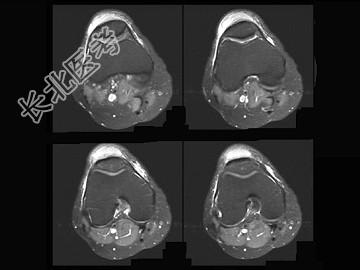

- 单项选择题男,20岁, 膝关节前方肿痛,轻度发红、发热, 结合图像,最可能的诊断是 ( )

E、髌前囊炎